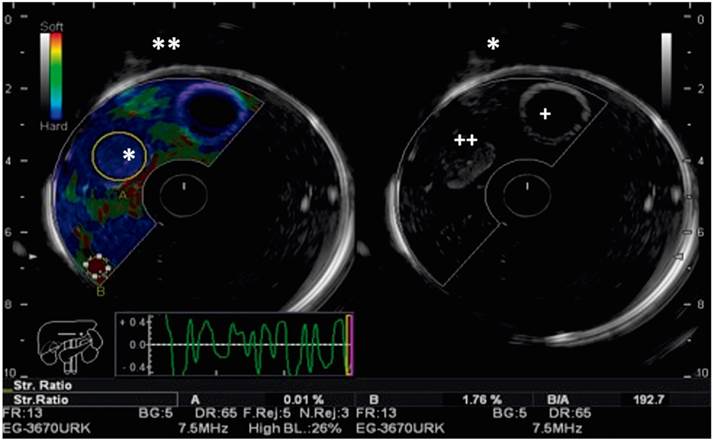

Figure 8 Elastography model and echoendoscopic view: the echogenic characteristics of a solid lesion are shown on the right (*), and its elastographic representation (**) are highlighted on the left.

Quantitative elastography is based on measurement of the speed of propagation of transverse shear waves. These waves are produced in the process of tissue compression and recovery to its original shape. 15 They are represented on heat maps that vary from blue which indicates stiffer tissues to red which indicates softer tissues. 17

The strain ratio is the ratio between the average tension measured in a solid lesion and the average tension of a similar area of healthy tissue or of tissue adjacent to the lesion. 18 The difference in deformation reflects the relative stiffness of the lesion, as shown in Figure 9. Various studies have related a stiff strain ratio of more than 20 to malignant lesions. 19,20